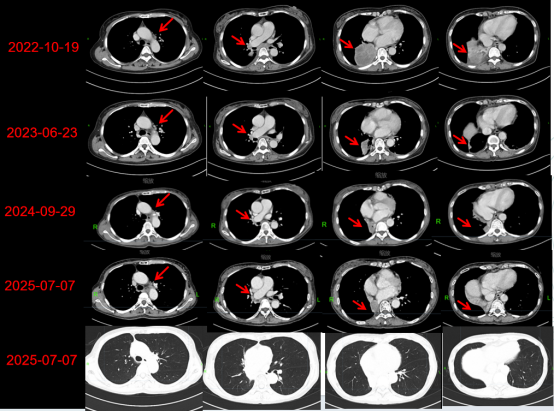

2022年10月,持续的头痛让王女士备受折磨,伴随而来的还有走路摇晃、轻微咳嗽。起初,她只当作寻常小恙,并未放在心上。然而,医院的CT检查结果击碎了所有侥幸:颅脑显示,左侧颞叶、右侧额叶、顶叶等多处出现异常信号,考虑为多发脑转移瘤,肿瘤压迫导致左侧侧脑室变形,并伴有脑水肿;胸部则发现右肺下叶有肺癌病灶,且已发生肺门、纵隔淋巴结转移。随后的病理活检,确诊为肺腺癌。更令人揪心的是,当时的基因检测结果为"未见敏感突变”,这意味着她无法从疗效显著的靶向治疗中获益。

2023年6月,振奋人心的消息传来:王女士的复查结果显示,颅内大部分肿瘤已完全消失,仅个别病灶呈囊性变;肺部病灶与转移的淋巴结也显著缩小;肿瘤标志物如癌胚抗原等关键指标大幅下降,部分已恢复正常。然而,聂大红教授团队并未因此松懈,考虑到肺部仍有残留病灶,存在复发风险,他们又及时为王女士制定了针对肺部残留病灶的姑息性放疗方案,以巩固疗效。在此期间,免疫治疗持续进行,构筑起一道坚固的抗癌防线。

此次放疗后,团队坚持对王女士进行严密随访。2025年7月的最新复查结果令人欣喜:右侧颞叶的新发转移灶几乎完全消失,既往颅内放疗后的病灶仅存轻微囊性变等治疗后改变,无任何明确的实性肿瘤残留;肺部病灶则几乎完全消退,且未出现放射性肺炎、免疫性肺炎等常见并发症,肿瘤标志物也持续维持在理想水平。

患者病灶变化图

在王女士的整个治疗过程中,团队始终以患者为中心,根据病情演变灵活调整策略:从最初的紧急颅内放疗,到后续的化疗免疫联合治疗,再到肺部残留病灶的巩固放疗,以及复发后的再程精准放疗,每一步都环环相扣、精准把控。不仅用顶尖的医疗技术为患者击退病魔,更用关怀与耐心抚平患者内心的惊涛骇浪,让王女士在抗癌的漫漫长夜中,始终能感受到温暖与希望。